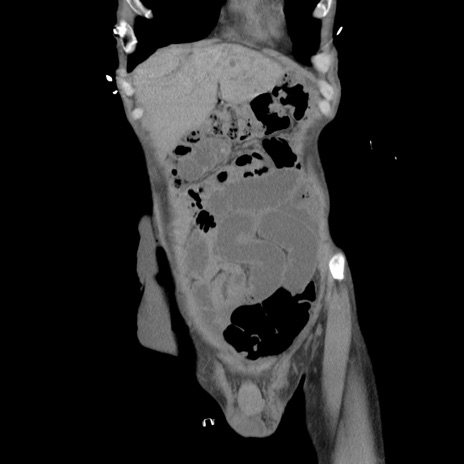

横断像

症例11(冠状断像)

【症例】 60歳代男性

【主訴】 下腹部痛

【現病歴】 本日夜中より下腹部痛の症状認め、受診。

【既往歴】 膀胱癌(膀胱全摘+尿管皮膚瘻術) 、胃癌術後

【身体所見】 BT 35.3℃、PR 58/min、BP 136/98mHg、腹部平坦、軟、腸蠕動音±、ストマ留置あり、左上腹部~正中部に圧痛あり、反跳痛なし。

【データ】WBC 5100、CRP0.01